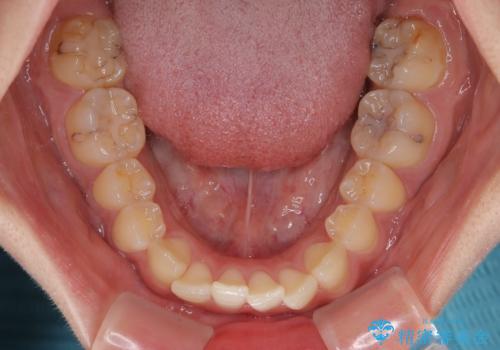

- 上下前歯のデコボコを気にして来院された患者様です。

ワイヤー矯正でもマウスピース矯正でも可能でしたが、短期間で、自身の手を煩わせることなく治療を行いたいとのことで、ワイヤー装置にて矯正治療を行うこととしました。

僅か8ヶ月という短期間で、綺麗な歯列に仕上がりました。